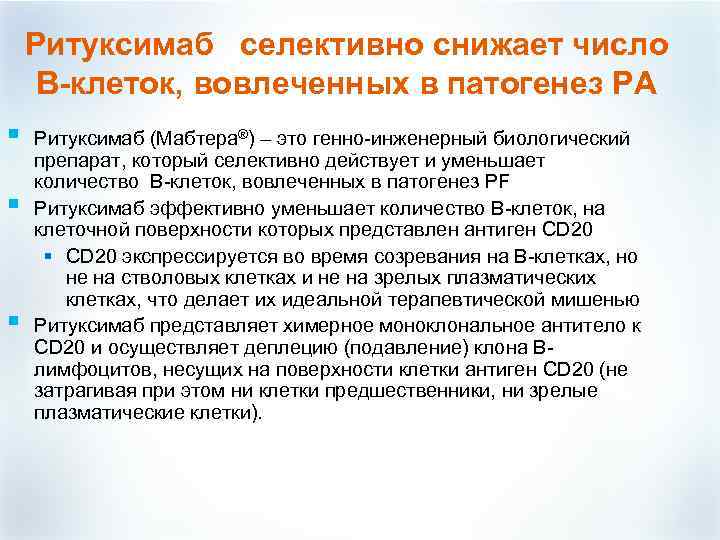

Ритуксимаб селективно снижает число B-клеток, вовлеченных в патогенез РА § § § Ритуксимаб (Мабтера®) – это генно-инженерный биологический препарат, который селективно действует и уменьшает количество B-клеток, вовлеченных в патогенез РF Ритуксимаб эффективно уменьшает количество B-клеток, на клеточной поверхности которых представлен антиген CD 20 § CD 20 экспрессируется во время созревания на B-клетках, но не на стволовых клетках и не на зрелых плазматических клетках, что делает их идеальной терапевтической мишенью Ритуксимаб представляет химерное моноклональное антитело к CD 20 и осуществляет деплецию (подавление) клона Влимфоцитов, несущих на поверхности клетки антиген CD 20 (не затрагивая при этом ни клетки предшественники, ни зрелые плазматические клетки).

Ритуксимаб селективно снижает число B-клеток, вовлеченных в патогенез РА § § § Ритуксимаб (Мабтера®) – это генно-инженерный биологический препарат, который селективно действует и уменьшает количество B-клеток, вовлеченных в патогенез РF Ритуксимаб эффективно уменьшает количество B-клеток, на клеточной поверхности которых представлен антиген CD 20 § CD 20 экспрессируется во время созревания на B-клетках, но не на стволовых клетках и не на зрелых плазматических клетках, что делает их идеальной терапевтической мишенью Ритуксимаб представляет химерное моноклональное антитело к CD 20 и осуществляет деплецию (подавление) клона Влимфоцитов, несущих на поверхности клетки антиген CD 20 (не затрагивая при этом ни клетки предшественники, ни зрелые плазматические клетки).